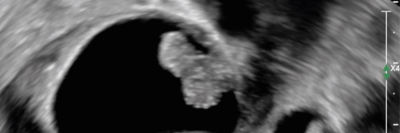

Ein Abstrich vom Gebärmutterhals wird auf ein Objektivträger geschmiert/© Tatiana Buzmakova / Getty Images / iStock (Symbolbild mit Fotomodellen), MRT des Beckens: Uterus und Ovarialtumoren/© Hosten AK et al. / all rights reserved Springer Medizin Verlag GmbH, Ultraschall eines Adnextumors/© Markus Hoopmann, Mehrere Personen erhalten Chemotherapie/© FatCamera / Getty Images / iStock (Symbolbild mit Fotomodellen), Subtypen des epithelialen Ovarialkarzinoms/© Springer Medizin, Frau mit Kopftuch und Infusion/© FatCamera / Getty Images / iStock (Symbolbild mit Fotomodell), Gewinner des Galenus-von-Pergamon-Preises 2025 in der Kategorie Specialist Care/© Marc-Steffen Unger, Frau bereitet einen Smoothie zu/© Tijana Simic / Getty Images / iStock (Symbolbild mit Fotomodell), Subkutane Injektion/© myskin / stock.adobe.com (Symbolbild mit Fotomodel), Eine ältere Frau bekommt eine intravenöse Therapie/© peopleimages.com / stock.adobe.com, Ärztin betrachtet Mammografie-Befund/© Gorodenkoff / stock.adobe.com (Symbolbild mit Fotomodellen), Frau bei Mammografie-Untersuchung/© Myroslava / Stock.adobe.com (Symbolbild mit Fotomodellen), Frau setzt sich ein Pflaster auf den Schenkel/© svetikd / Getty Images / iStock (Symbolbild mit Fotomodell), Lungenmetastasendiagnostik/© Krämer S. et al. / all rights reserved Springer Medizin Verlag GmbH, Verlagerung von Oberbauchorganen in den Thorax/© Koop H (Mit freundl. Genehmigung der Radiologischen Abteilung), Multiple Papeln auf der Hand bei chronischer Prurigo/© E. Steffens et al. doi.org/10.1007/s00105-023-05131-8 unter CC-BY 4.0, Hysterektomie/© nkeskin / Getty Images / iStock, Search Icon, Person setzt DNS-Probe in Maschine ein/© Vit Kovalcik / stock.adobe.com, Mann raucht Joint/© Daniel Sierralta / Westend61 / stock.adobe.com (Symbolbild mit Fotomodell), Blut in Toilette/© stylefoto24 / stock.adobe.com